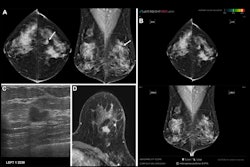

Investigators explored the impact of adding AI to mammogram screening exams. For those enrolled, the clinical practices applied a U.S. Food and Drug Administration-compliant AI software to their mammograms. An expert breast radiologist also provided a third, "safeguard review" in cases where there was discordance between the first reviewer and the AI.

All 10 practices saw a substantially higher CDR in enrolled women compared with unenrolled women. Of the overall CDR, researchers further noted a 21% increase in cancer detection that they attributed to the AI program. They credited the remaining 22% increase in cancer detection to the fact that higher-risk patients chose to enroll more frequently.

Cancer detection rate, recall rate, and positive predictive value (PPV1) were calculated per practice using routine Mammography Quality Standards Act methodology, the study noted. Overall, the recall rate was 21% higher for enrolled versus unenrolled women at 10.9% versus 8.8%, and the PPV1 was 15% higher at 5.4% versus 4.6%.